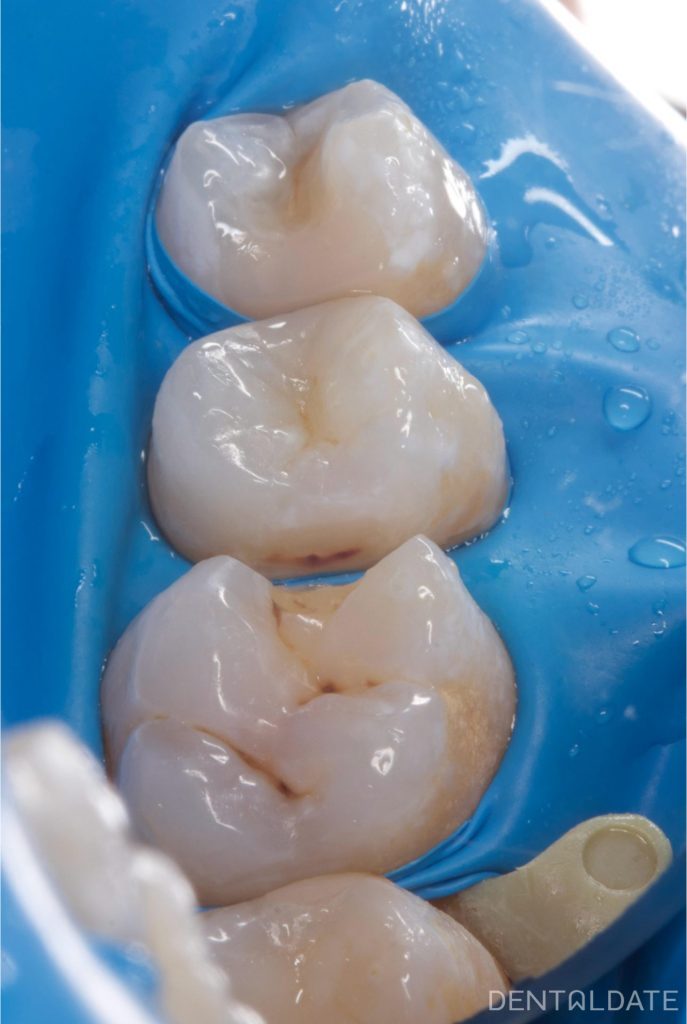

During treatment, decay was also discovered on a neighbouring tooth.

Once all infected surfaces have been cleaned, the teeth are prepared for restoration.